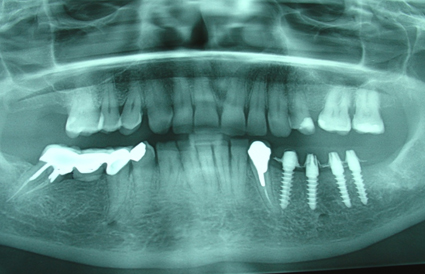

Generalmente, respetando el encerado diagnóstico se confecciona una prótesis de resina acetálica, que se articula en boca, se pule y se cementa con Temp Bond (NR); y se realiza una Rx panorámica de control.(F3 y F4)

En las visitas de seguimiento, se analizará el comportamiento estético y funcional de dicha prótesis temporaria pues será la base para la confección del puente fijo definitivo.